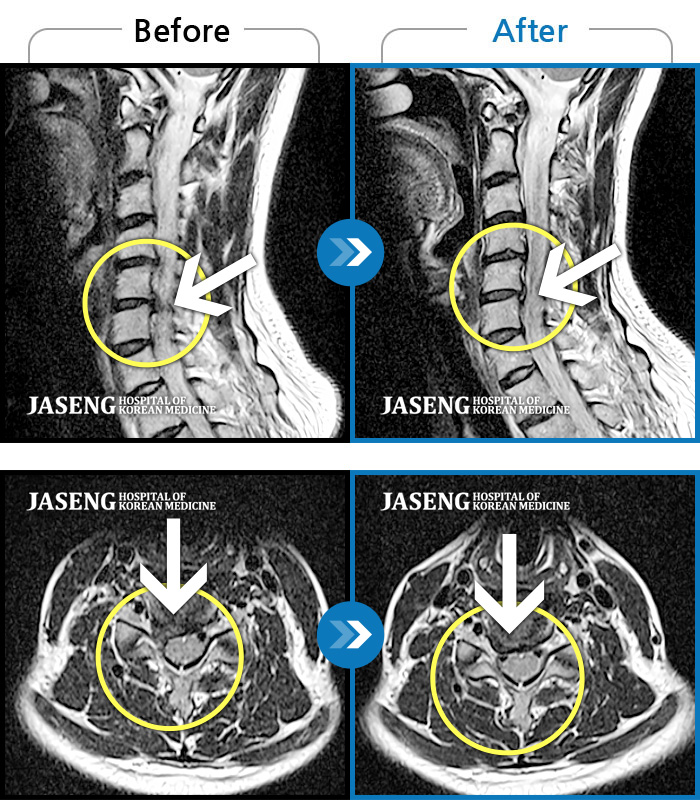

MRI 치료사례

목을 들면 오른쪽 목 통증과 어깨 통증 발생, 오른쪽 어깨에서 팔꿈치까지 통증